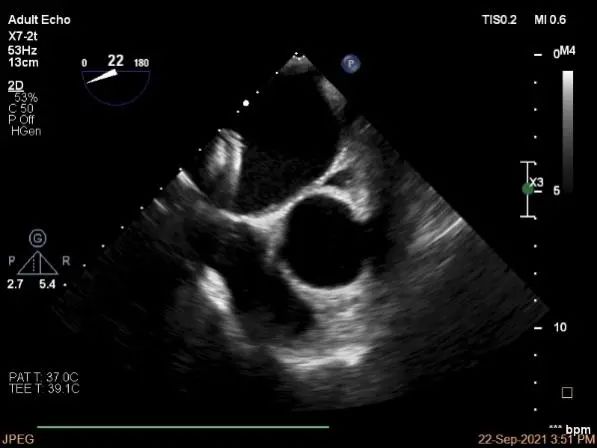

术前超声评估

术中超声

P2区脱垂,宽14.8mm,Gap:3.3mm

3D-color,返流重度,3+级

麻醉状态下左肺静脉血流频谱

MVA:6.67cm²

房间隔穿刺点选择

穿刺高度:4.3cm